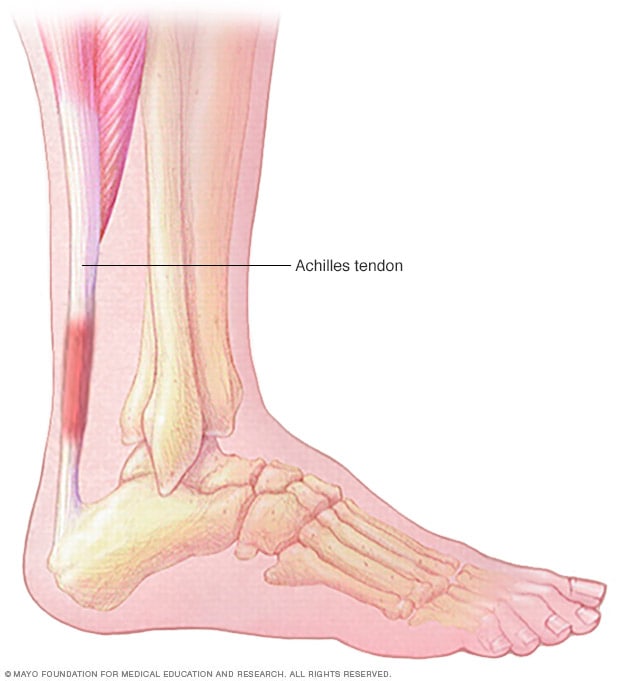

Product Item: Swollen achilles tendon treatment dealsAchilles tendon injuries healthdirect deals, Achilles Tendinitis Symptoms Treatment deals, How to Relieve Achilles Tendonitis in SECONDS deals, Achilles Tendinitis OrthoInfo AAOS deals, Achilles Tendinitis Exercises to Heal and Strengthen Your Tendon deals, Achilles Tendon Pain Causes Treatments Prevention deals, Achilles tendon Overview Mayo Clinic Orthopedics Sports Medicine deals, Achilles Tendonitis Symptoms and Treatment Caruso Foot and Ankle deals, Tendinopathy Symptoms Causes Treatment deals, Achilles Tendinitis OrthoInfo AAOS deals, Chronic Achilles Tendon Pain Diagnosis Treatment HSS deals, Know the Symptoms of Achilles Tendonitis Tendinopathy Gait Happens deals, Achilles tendinopathy Symptoms causes and treatment Bupa UK deals, Achilles Tendon Injuries deals, Swollen Achilles tendon Why does it swell and when can I exercise deals, Heal Your Achilles Tendonitis At Home Achilles Tendon Treatment deals, Achilles Tendonitis FootEducation deals, Achilles Tendinopathy Symptoms Treatments Recovery deals, Achilles Tendinopathy Causes Symptoms Treatment The Feet People Podiatry deals, How to fix Insertional Achilles Tendonitis deals, Achilles tendinitis Symptoms causes Mayo Clinic deals, Back of Achilles Tendon Heel Pain Shoes Orthotics Home Treatment deals, Achilles Tendonitis Causes Symptoms Signs Gleneagles Hospital deals, Achilles Tendinopathy NHS Lanarkshire deals, Achilles Tendinitis in Children Causes and Treatment deals, Achilles Tendonitis Common Symptoms Diagnosis and Treatment deals, Achilles Tendinitis Types Symptoms Causes Diagnosis Treatment and More deals, Achilles Tendinitis River Forest Rheumatoid Arthritis Elmhurst deals, Achilles tendinopathy is when you have micro tears in the tendon deals, Achilles swelling sales pain deals, Achilles Tendon Burning Pain Treatment Achilles Tendonitis deals, Achilles Tendinopathy Causes Symptoms Treatment The Feet People Podiatry deals, Exercises for Achilles pain Three gentle moves to get your rehab going deals, Achilles Tendinosis Treatment Symptoms and More deals, Achilles deals tendon swelling deals.